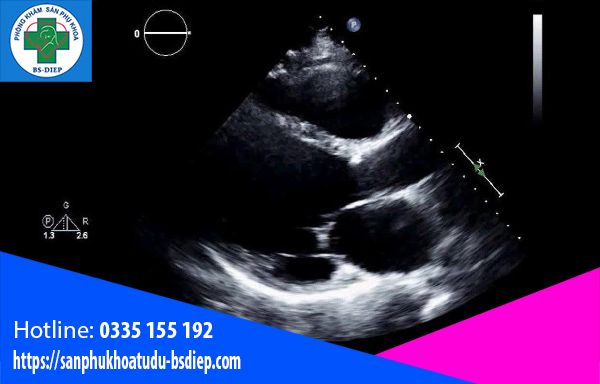

Nếu có mẹ bầu nói rằng mẹ có cảm nhận được tim thai thì đó chỉ là thai máy – các hoạt động của thai nhi trong bụng mẹ, không phải hoạt động của tim thai. Tóm lại, mẹ chỉ có thể nghe nhịp đập và nhìn tim thai (theo hướng dẫn của bác sĩ) khi siêu âm tại phòng khám/bệnh viện.

Mẹ bầu có thắc mắc, nếu việc mẹ có cảm nhận được tim thai là bất khả thi thì mẹ có thể thông qua bác sĩ để biết được tình trạng của tim thai vào thời gian nào không? Mẹ bầu có thể thông qua siêu âm để nghe được nhịp tim của thai nhi sớm nhất vào tuần thứ năm. Nếu mẹ bầu không nghe được nhịp đập của tim thai thì đừng vội lo vì nghe tim thai rõ nhất sẽ rơi vào khoảng tuần thứ 6 hoặc thứ 7.